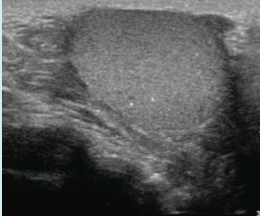

intestinal ischemia

07/22/2016

Clifton C. Lee, MD; Hanh K. Le, MD, MS

A 5-month-old boy presented with sudden onset nonbloody, nonbilious vomiting.